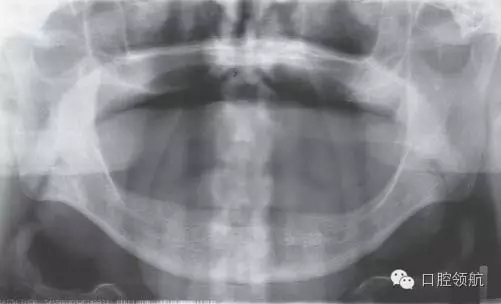

初診時,口內(nèi)所見(圖1),曲面斷層片顯示(圖2),患者植入?yún)^(qū)骨量不足,前庭溝深度不足,附著齦的量不足。

圖2 初診時曲面斷層影像。